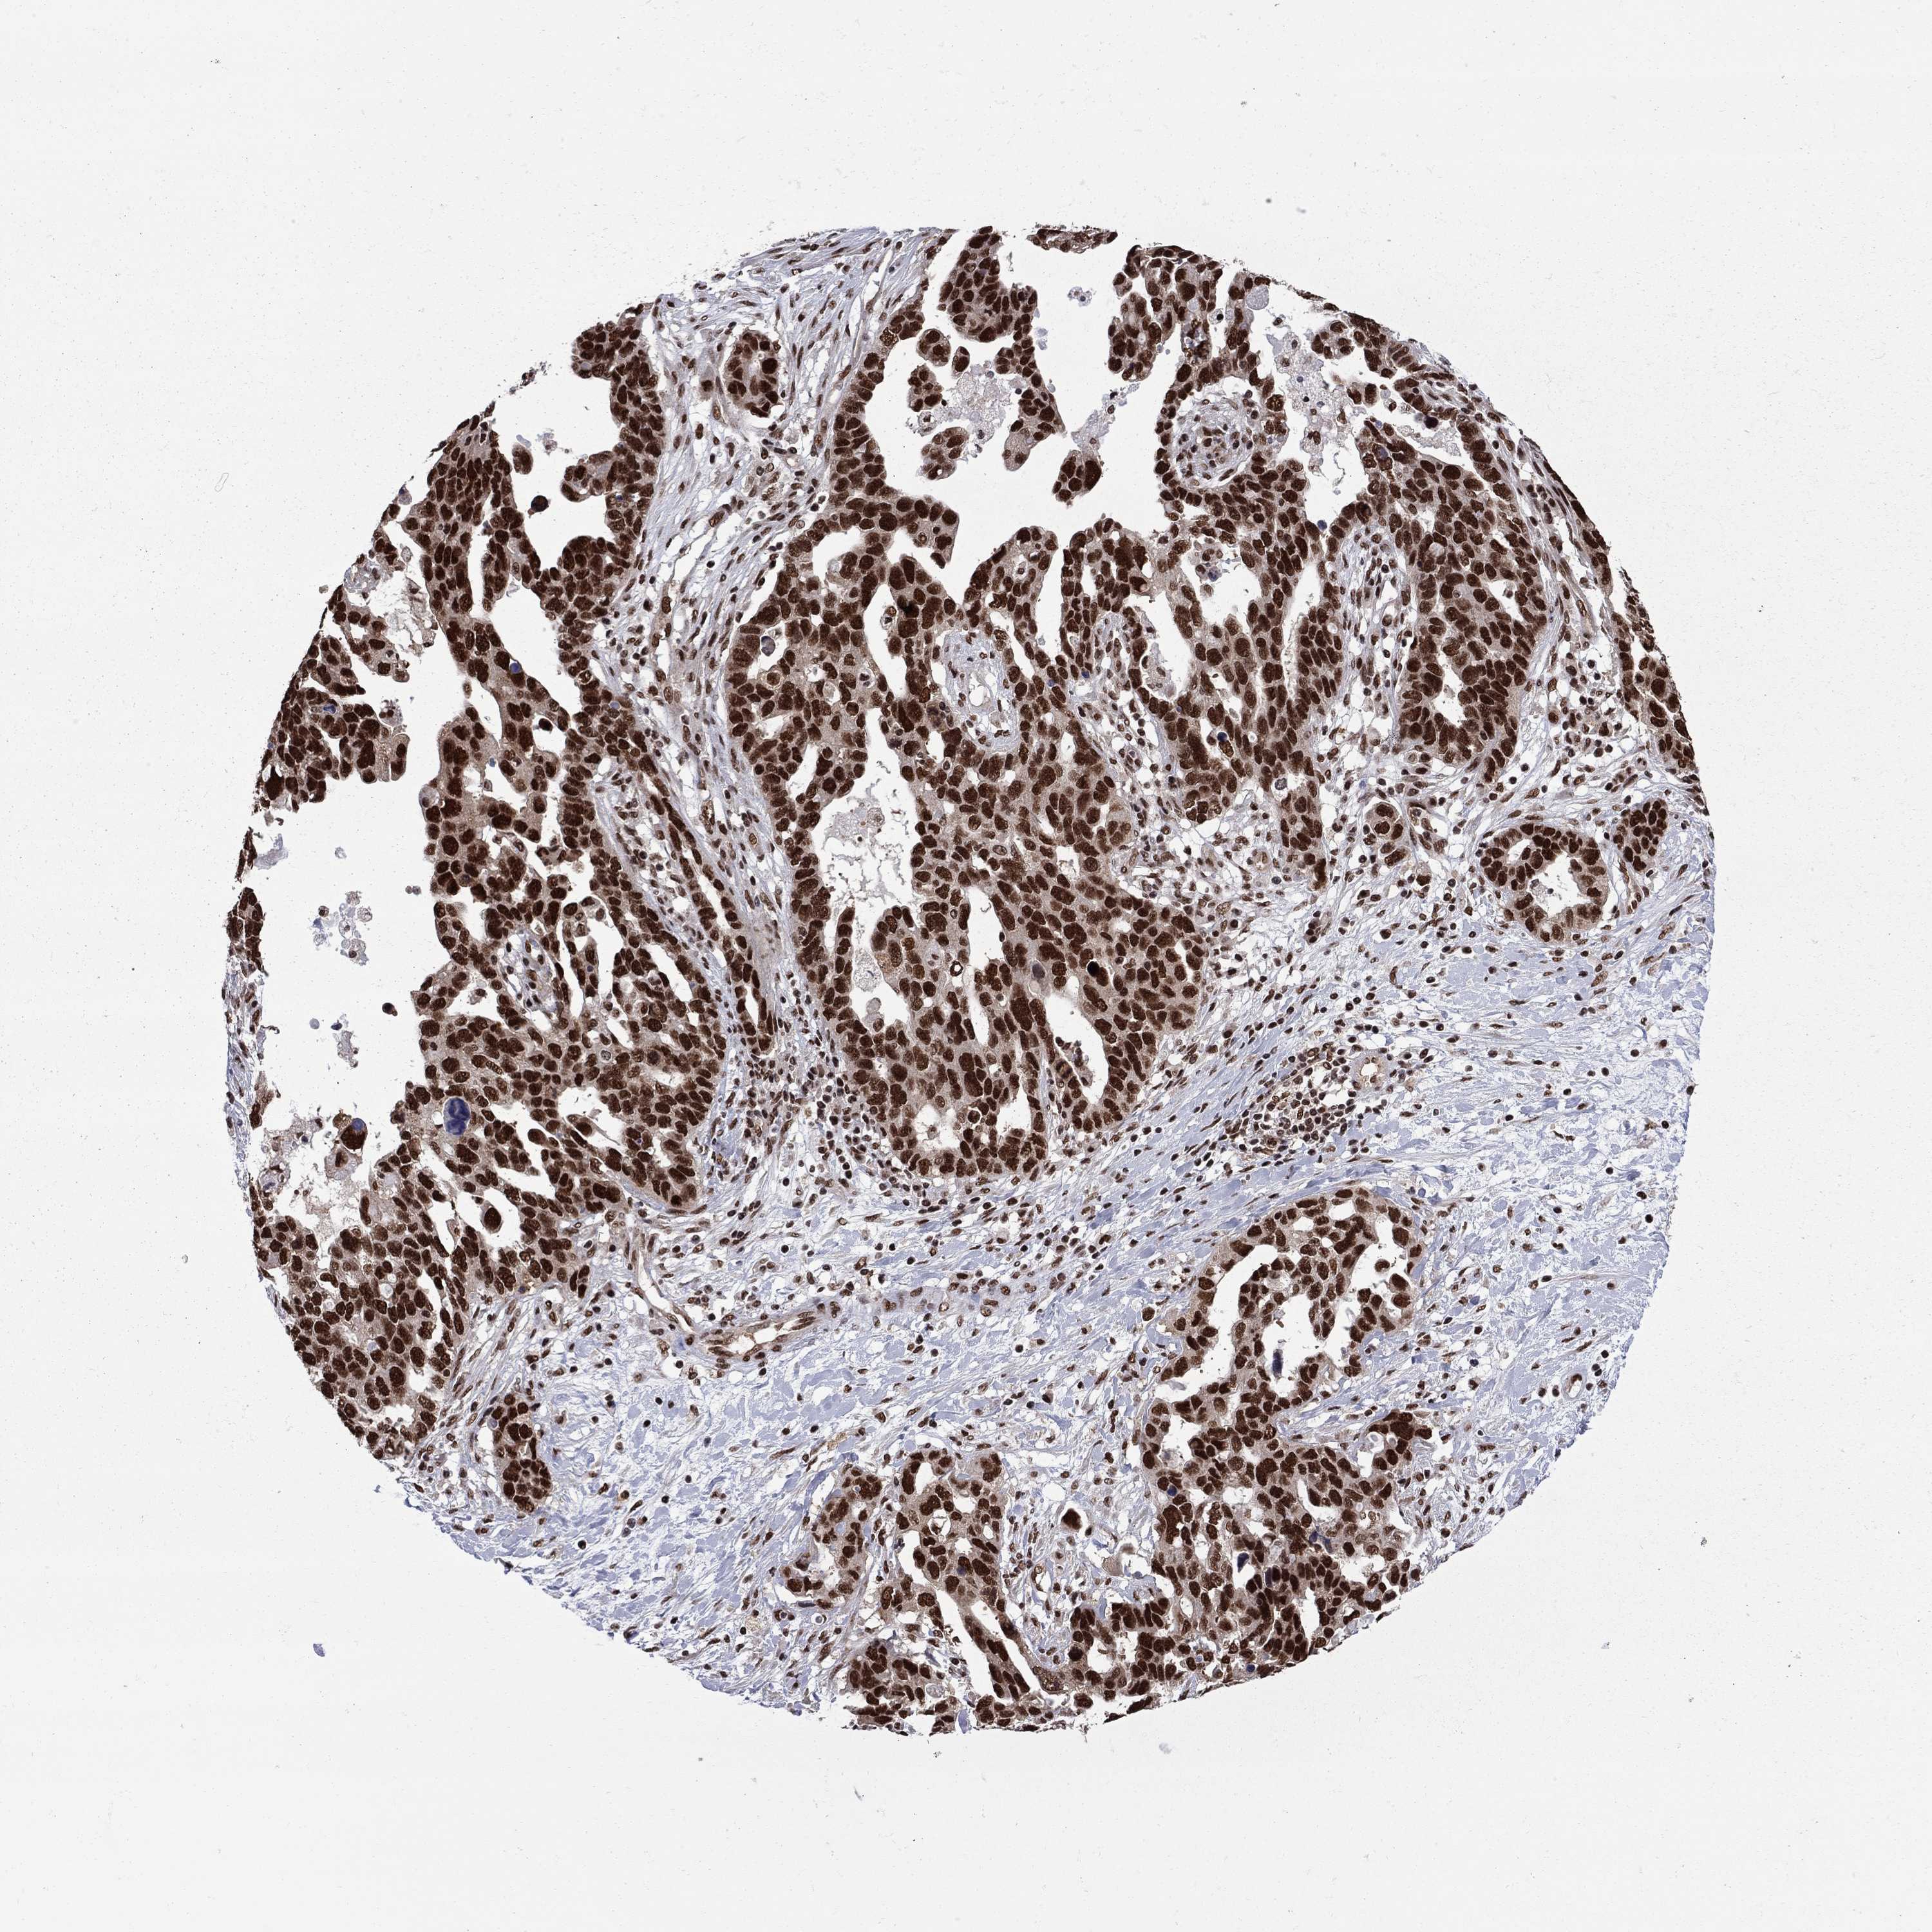

OVARIAN CANCER - Protein expressioni

A mouse-over function shows sample information and annotation data. Click on an image to view it in a full screen mode. Samples can be filtered based on level of antibody staining by selecting one or several of the following categories: high, medium, low and not detected. The assay and annotation is described here.

Note that samples used for immunohistochemistry by the Human Protein Atlas do not correspond to samples in the TCGA dataset.

Antibody stainingi

Antibody staining in the annotated cell types in the current human tissue is reported as not detected, low, medium, or high, based on conventional immunohistochemistry profiling in selected tissues. This score is based on the combination of the staining intensity and fraction of stained cells.

Each image is clickable and will lead to virtual microscopy that enables deeper exploration of all samples and also displays staining intensity scores, fraction scores and subcellular localization as well as patient and tissue information for each sample.

Antibody HPA068802

Staining

High

Medium

Low

Not detected

Intensity

Strong

Moderate

Weak

Negative

Quantity

>75%

75%-25%

<25%

None

Location

Nuclear

Cytoplasmic/membranous

Cytoplasmic/membranous,nuclear

Cystadenocarcinoma, serous, NOS

Cystadenocarcinoma, mucinous, NOS

Carcinoma, endometroid